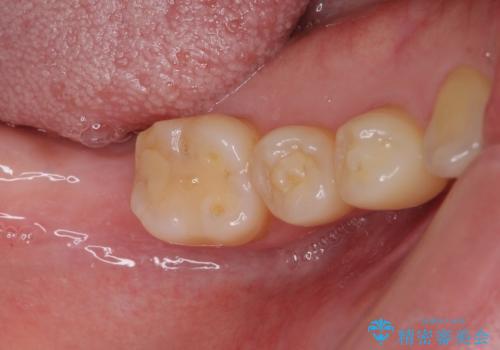

抜歯されたままの奥歯 ストローマンインプラントによる欠損補綴治療

- 抜歯してから放置されている右下の奥歯へのインプラント治療を希望して来院された患者様です。

ストローマン社のSLActiveというインプラントを使用し、インプラント埋入からクラウンが装着されるまで3ヶ月弱という短期間で終えることができました。

咬み心地はもちろん、清掃性もご自分の歯とほとんど変わらない状態となり、患者様には大変満足していただきました。